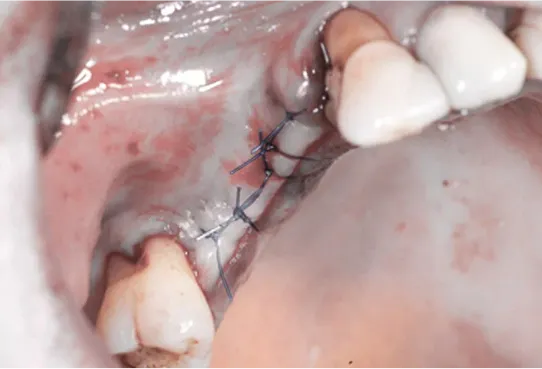

ODBUDOWA UBYTKU PO USUNIĘCIU ZĘBA - SOCKET PRESERVATION

To prosta, szybka i bezpieczna technika odbudowy kostnej zębodołu po ekstra-kcji zęba. Znana wcześniej, lecz opisana dopiero w ramach międzynarodowego konsensusu z 2010 roku (prof. Lindhe, prof. Araujo)

Zabieg odbudowy zębodołu powinno się wykonać możliwe jak najszybciej po usunięciu zęba. Jego celem jest odbudowa naturalnej objętości kości w miejscu utraconego zęba, a następnie szybkie wprowadzenie implantu. Najlepsze rezul-taty uzyskuje się przy zastosowaniu biomateriału w formie bloczków kolageno-wych lub granulatu, które dają trwałe efekty odbudowy oraz optymalną funkcję i estetykę odtworzonych koron zębów na wszczepionym implancie.